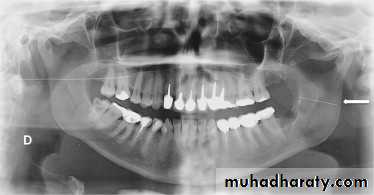

Management of retained needles requires locating the broken fragment through panoramic, computed tomographic (CT) scan or CBCT. The treatment options should be discussed with the patients. Retrieval usually is performed under general anesthesia. For broken needles embedded in the pterygo-mandibular space an intraoral approach through a vertical incision along the anterior border of the mandible,

extending inferiorly to the external oblique ridge, followed by sub-periosteal dissection along the medial aspect of the ramus of the mandible to identify bony landmarks (lingula), which can be used as

reference during exploration and also provides greater protection to the inferior alveolar and lingual nerves, supra-periosteal blunt dissection may be needed to identify the needle.